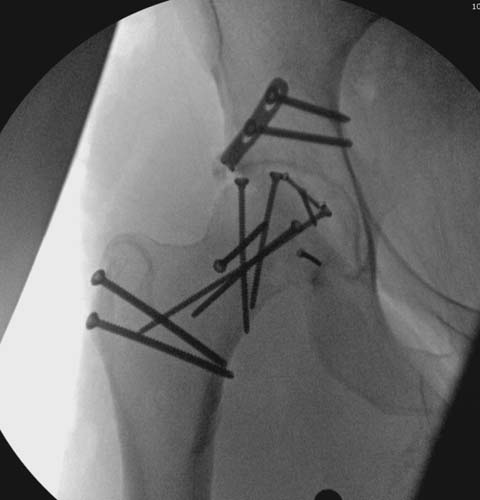

Уважаемые коллеги добрый вечер! Хотелось бы узнать ваше мнение о возможных ранних сроках наступления асептического некроза или коксартроза при данном виде оперативного лечения, может кто-то уже оперировал данную патологию и есть наблюдения. Случай практически идентичный описанный в январе 2015 на ортофоруме Никитой Николаевичем Заднепровским. Молодой человек 20 лет ДТП 23.02.2015, Диагноз: Сочетанная травма. Закрытый переломо-вывих головки и перелом заднего края вертлужной впадины (Pipkin4) правой бедренной кости. Открытый подтаранный вывих правой стопы. При поступлении в ЦРБ вправление вывиха головки бедра и подтаранного вывиха стопы.

Далее перевод к нам в Травмоцентр и 03.03.2015. через 8 дней операция, выполнен остеосинтез головки 3-мя самокомпрессирующими винтами Autofix под разными углами с погружением в субхондральный слой. Доступ Kocher-Langenbeck с флип-остеотомией большого вертела и задним хирургическим вывихом головки бедра. В полости сустава два свободно-лежачих фрагмента хряща головки, которые были удалены. На снимках виден дефект хряща головки после репозиции. Небольшой фрагмент заднего края фиксирован двумя спонгиозными винтами. Далее шов раны с дренированием. На 2 сутки пациент поворачивался на здоровый бок с валиком между ног, на 4 сутки сидел в кровати и на 6 сутки ходил с помощью костылей.